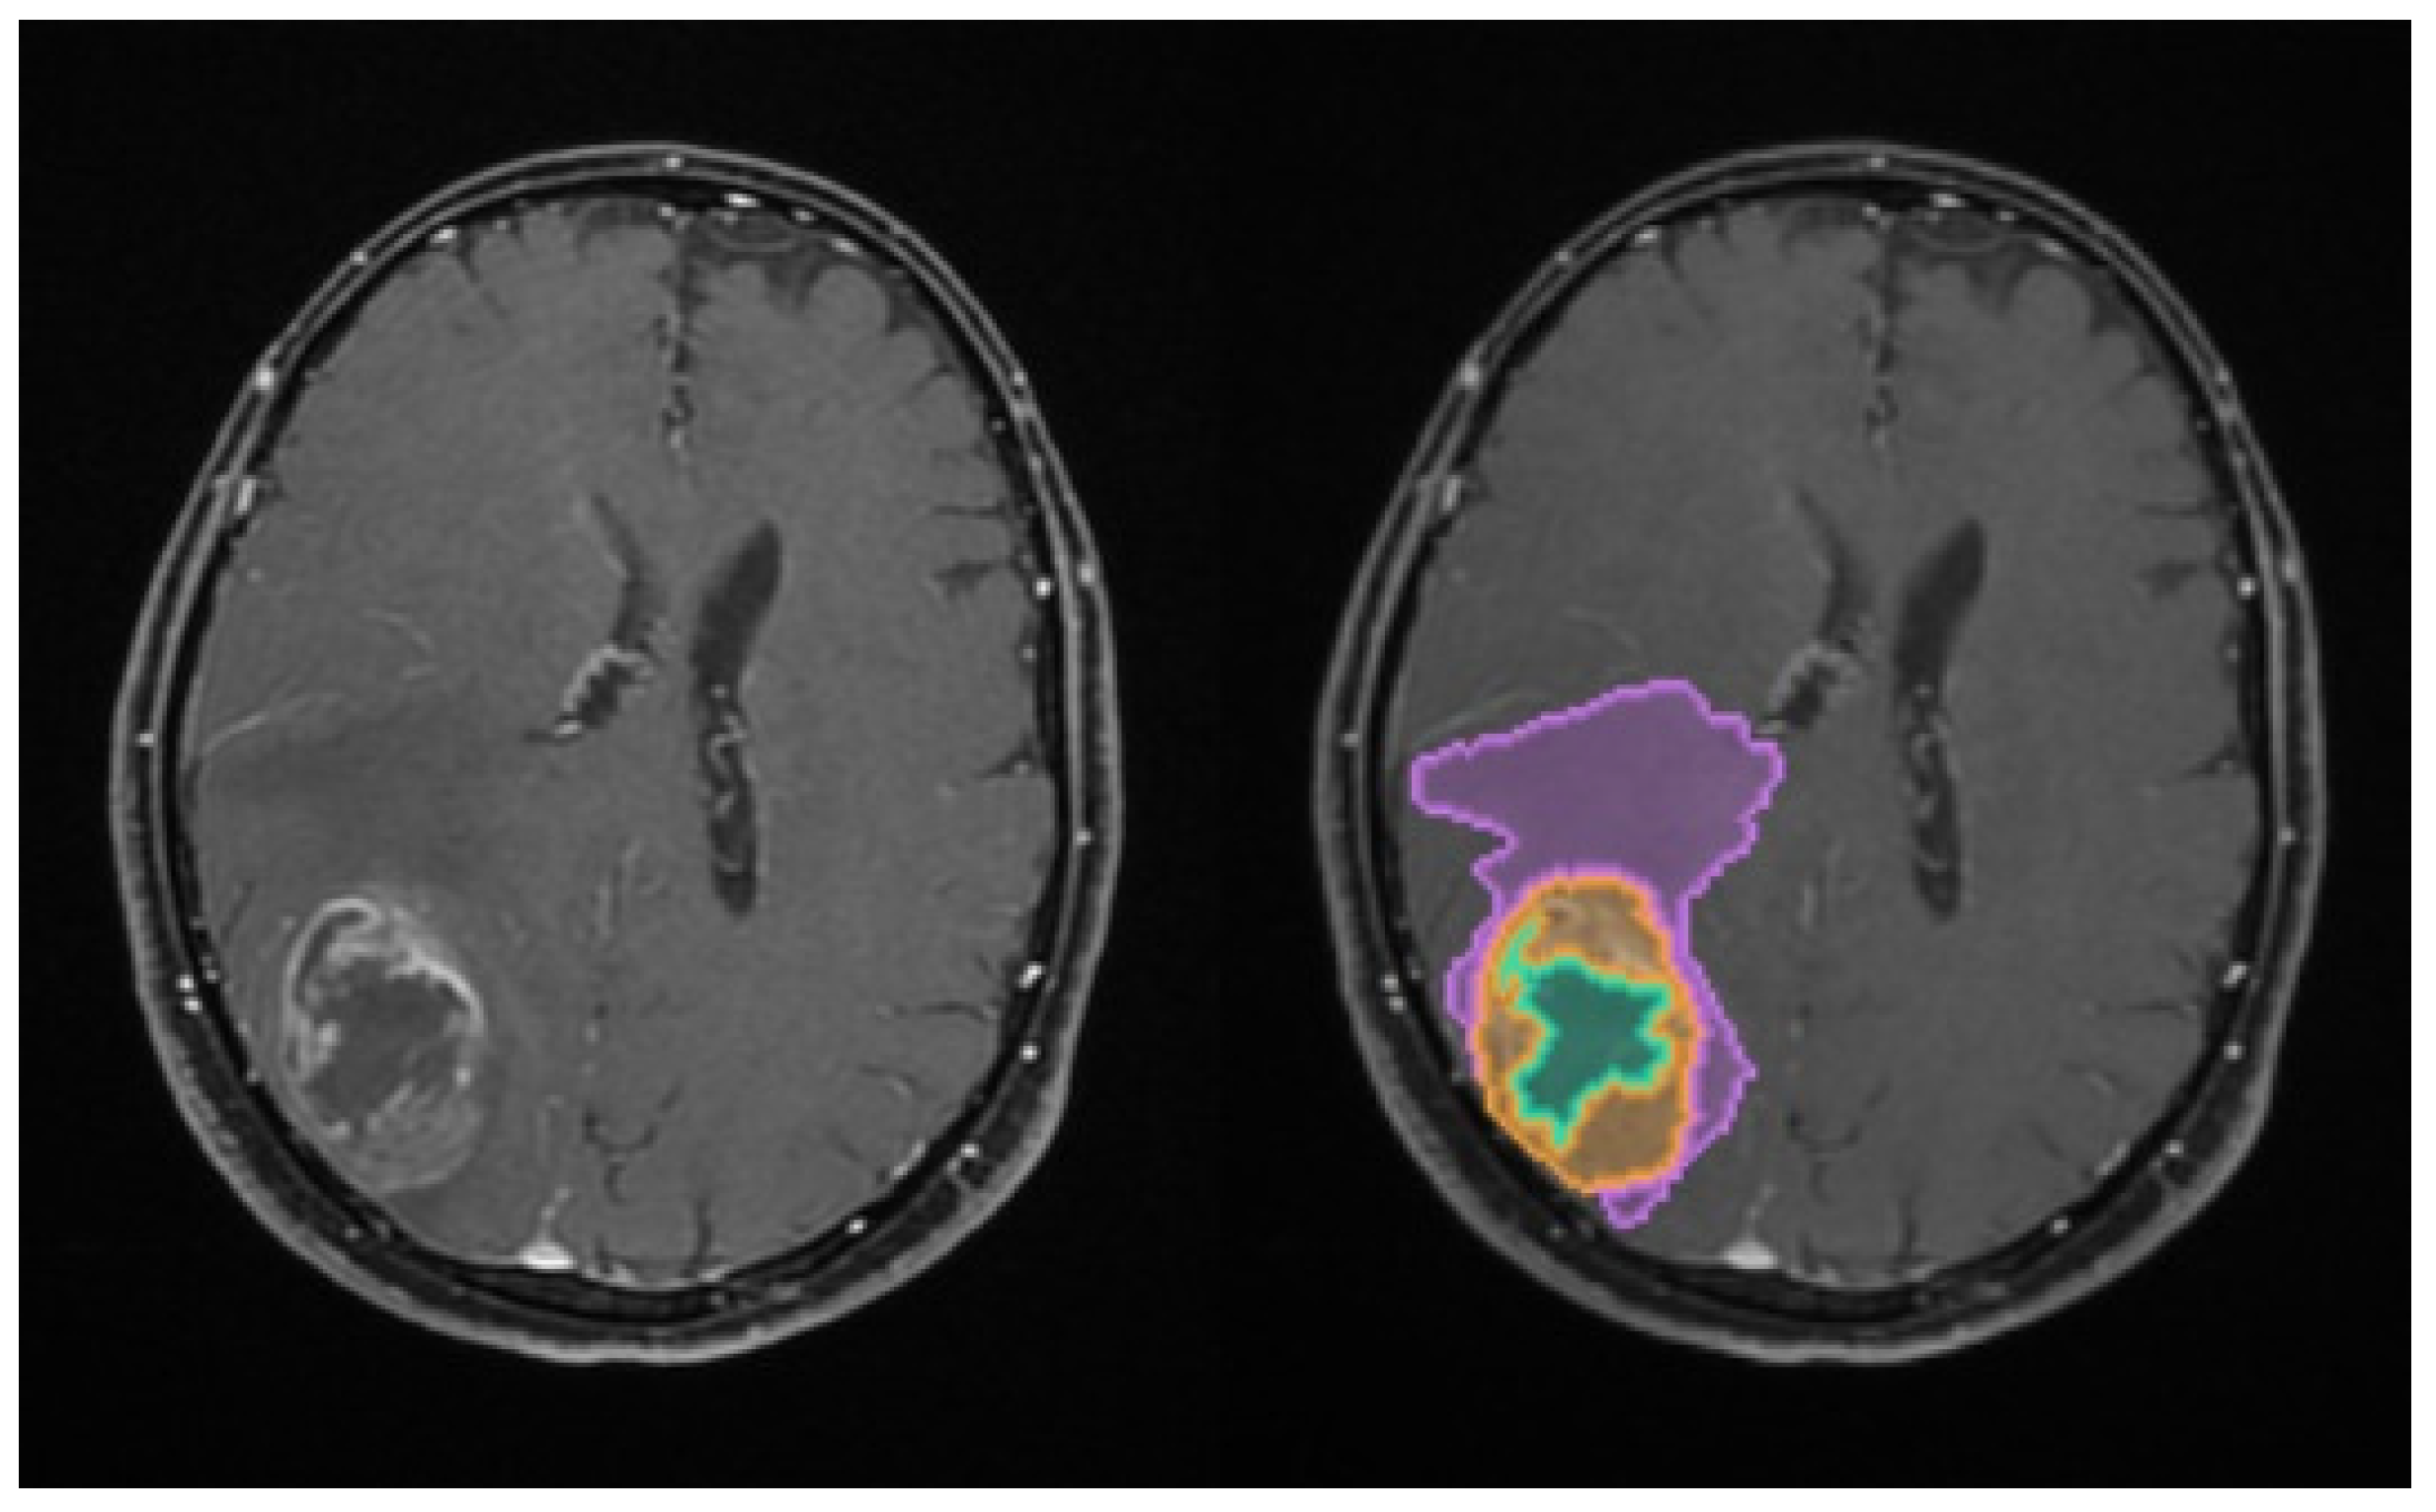

The total tumoral volume was thus partitioned into these three distinct sub-compartments, with the resulting Digital Imaging and Communication in Medicine (DICOM)-processed outputs illustrated in Figure 1.

Figure 1.

Illustration of the automated volumetric analysis of contrast-enhanced T1-weighted axial MRI sequences using the mdbrain software (scale 1:20). The segmented regions include the necrotic core (green), the contrast-enhancing tumor component (orange), and the perilesional edema (purple) (approval was obtained from the Ethics Committee of the University of Medicine and Pharmacy “Grigore T. Popa” Iasi).